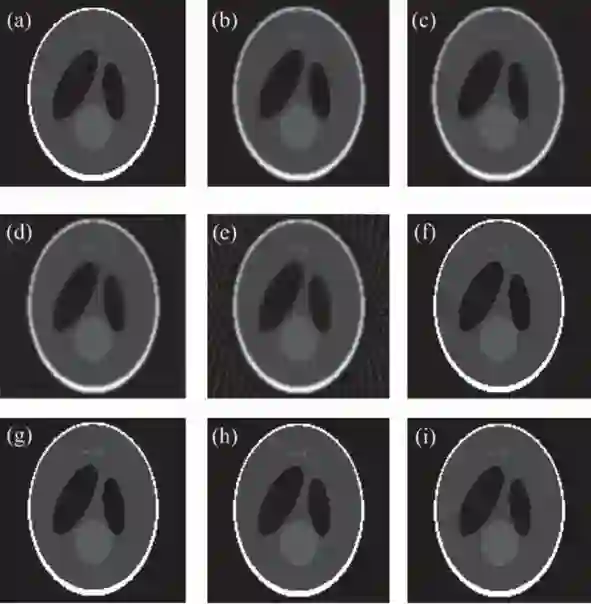

实验结果表明:与解析重建算法FDK相比,提出的算法在投影数较少的情况下,仍能获得较好的重建图像质量(见图1);与两种现有的基于TV正则化的迭代重建算法(ASD-POCS,EM-TV)相比,所提算法收敛速度提高6倍以上,且表现出更强的图像去噪和边缘保持能力(见图2)。此外,采用GPU加速手段使得上述迭代算法的重建时间大为减少(见表1)。

图1. 解析算法与3DA-TVAL3算法的重建结果。(a)Sheep-Logan体模的原图像;(b-e)360,180,90,60个投影角情况下,解析算法FDK的重建结果;(f-i)360,180,90,60个投影角情况下,3DA-TVAL3算法的重建结果。